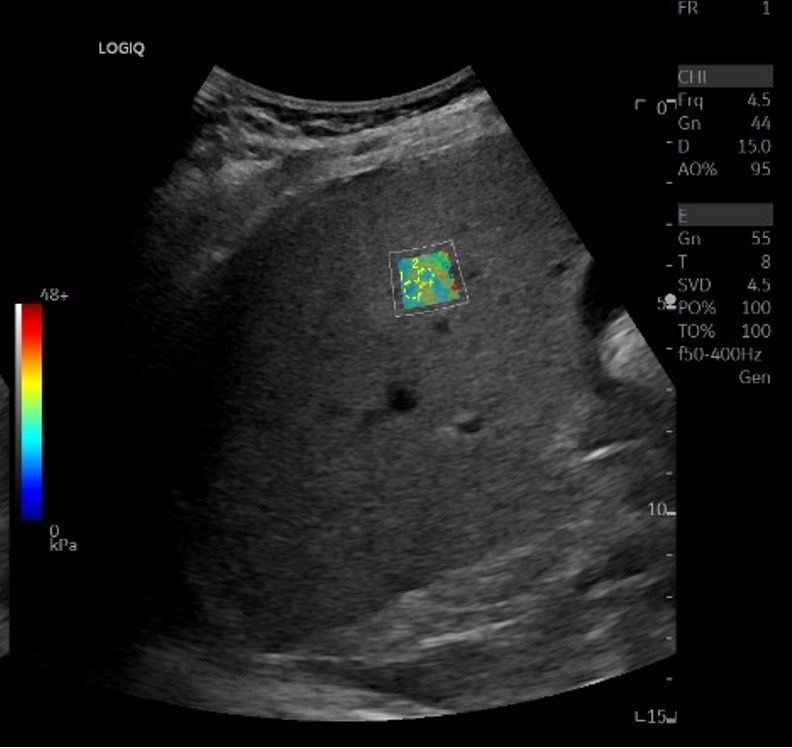

In an interesting turn of events, Dr Fink, alongside his student Mickael Tanter, recognised the potential of this technology in the realm of medical diagnosis. Their ingenuity led to them developing and patenting a technique called ‘shear wave elastography.’ This technique used shear waves to identify subtle differences in the elasticity of human tissues and displayed them in the form of real-time colour-coded maps. These maps offered a non-invasive means to identify diseased tissues within the body, a truly transformative advancement in medical imaging.

The rest, as they say, is history. Over the years, ultrasound elastography has dramatically transformed how we assess a variety of pathologies, offering a non-invasive, more comfortable alternative to traditional invasive procedures.

Today, ultrasound elastography is the cornerstone of assessment of liver fibrosis, lymph nodes, cancers of the thyroid, breast and prostate, as well as in musculoskeletal imaging in the evaluation of muscles and tendons. So, the next time someone asks you to do a ‘FibroScan’, smile and think about how it all started – with an endeavour to measure the softness of cheese!